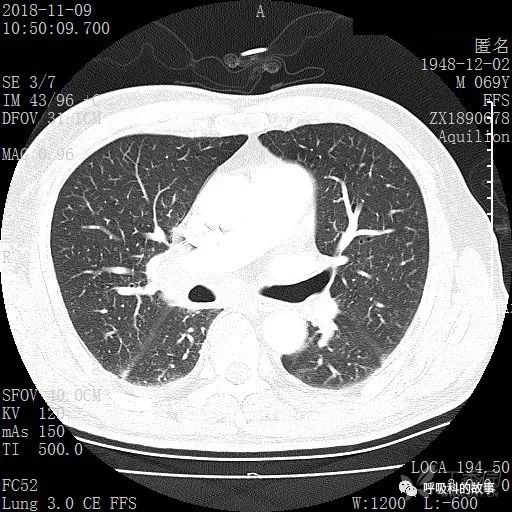

肺窗CT